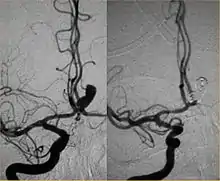

Intra-cranial angioplasty and stent of basilar artery stenosis

From the early 2000s, intracranial stents were used to prevent the coils inside the aneurysmal sac from protruding into the parent artery.[11][12] Flow diversion devices were later developed, with the function of reconstructing the vessel's normal anatomy without directly closing the aneurysm neck and therefore preserving side branches and preventing ischemia.[13] The sole stenting[14] procedure involves the insertion of a stent only (without any coils) into the vessel that has an aneurysm.[15]